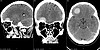

– Для расчета оптимальной траектории использовалась нейронавигация, позволившая точно определить локализацию опухоли и свести к минимуму повреждение окружающего мозгового вещества. Опухоль была удалена полностью. Радикальность удаления и отсутствие послеоперационных осложнений подтвердила контрольная компьютерная томограмма. У пациентки сохранены все двигательные, чувствительные, мнестические функции, кроме того достигнут и хороший косметический результат, – сообщил заведующий отделением.